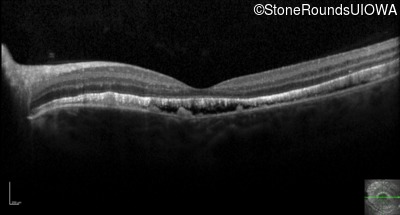

Optical Coherence Tomography - Right - 20/100 sc

Exemplar / OCT Stack

OCT Stack